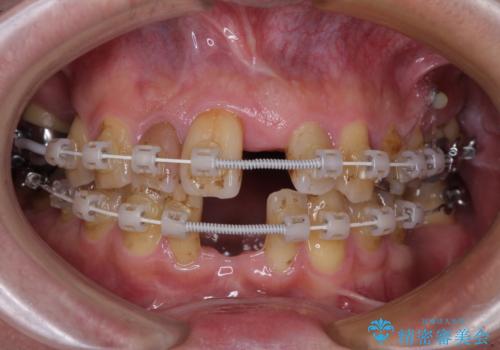

- むし歯治療途中で放置された歯が多く、スペースができたり歯が寄って来たりしているのを気にして来院された患者様です。

矯正治療を行いながら、欠損部はインプラントによる補綴治療を希望されたため、補助装置を用いたワイヤー矯正によりスペースを確保しながら歯列を整え、適宜インプラントを埋入していくこととしました。

在宅勤務のため、前歯にスペースが長期間できることに対して特に問題はないとおっしゃったため、スペースはそのままに治療を進めていくこととしました。